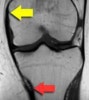

MRI : 무릎 내측 측부인대 손상(Medial collateral ligament injury, MCL injury)

MRI는 보다 정확한 병적상태를 파악하는 데 도움을 줍니다.